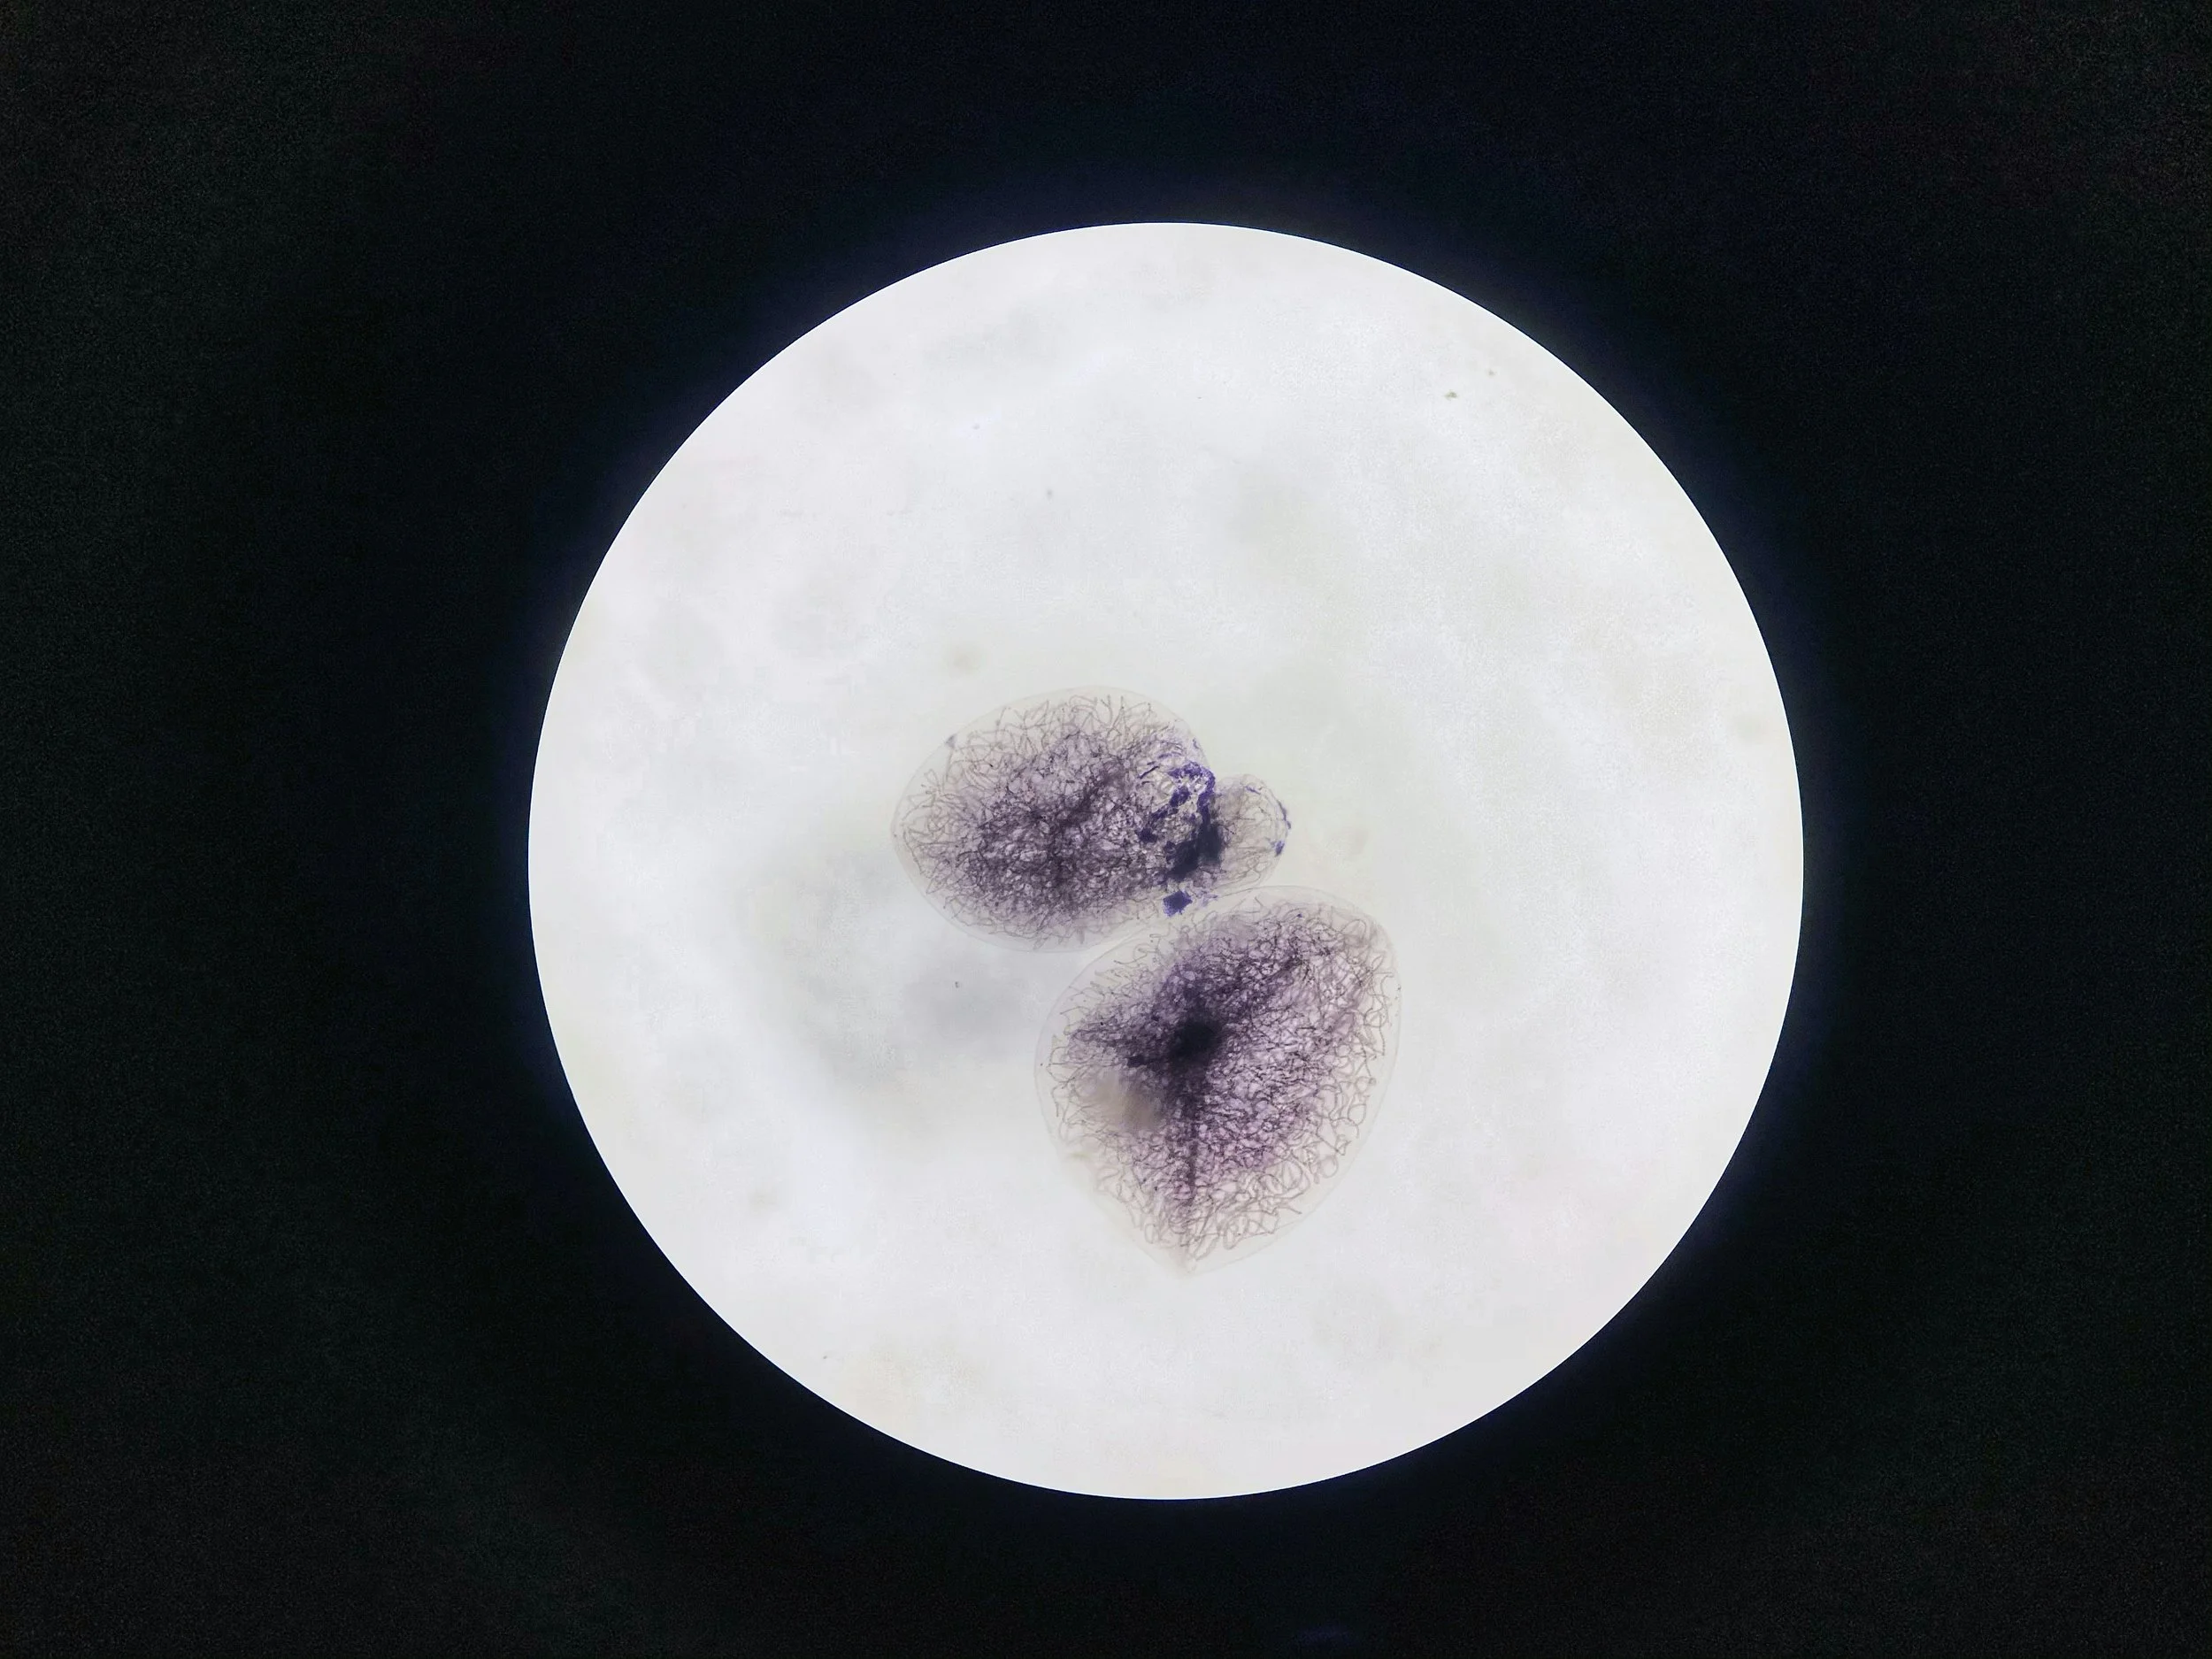

An embryo after fertilisation - Unsplash